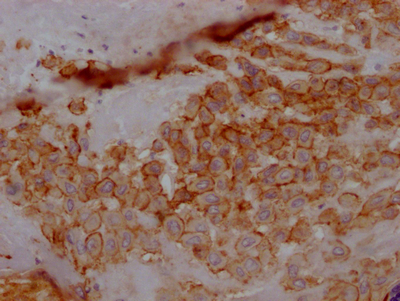

• IHC image of CSB-RA902876A0HU diluted at 1:100 and staining in paraffin-embedded human placenta tissue performed on a Leica BondTM system. After dewaxing and hydration, antigen retrieval was mediated by high pressure in a citrate buffer (pH 6.0). Section was blocked with 10% normal goat serum 30min at RT. Then primary antibody (1% BSA) was incubated at 4℃ overnight. The primary is detected by a Goat anti-rabbit IgG polymer labeled by HRP and visualized using 0.05% DAB.